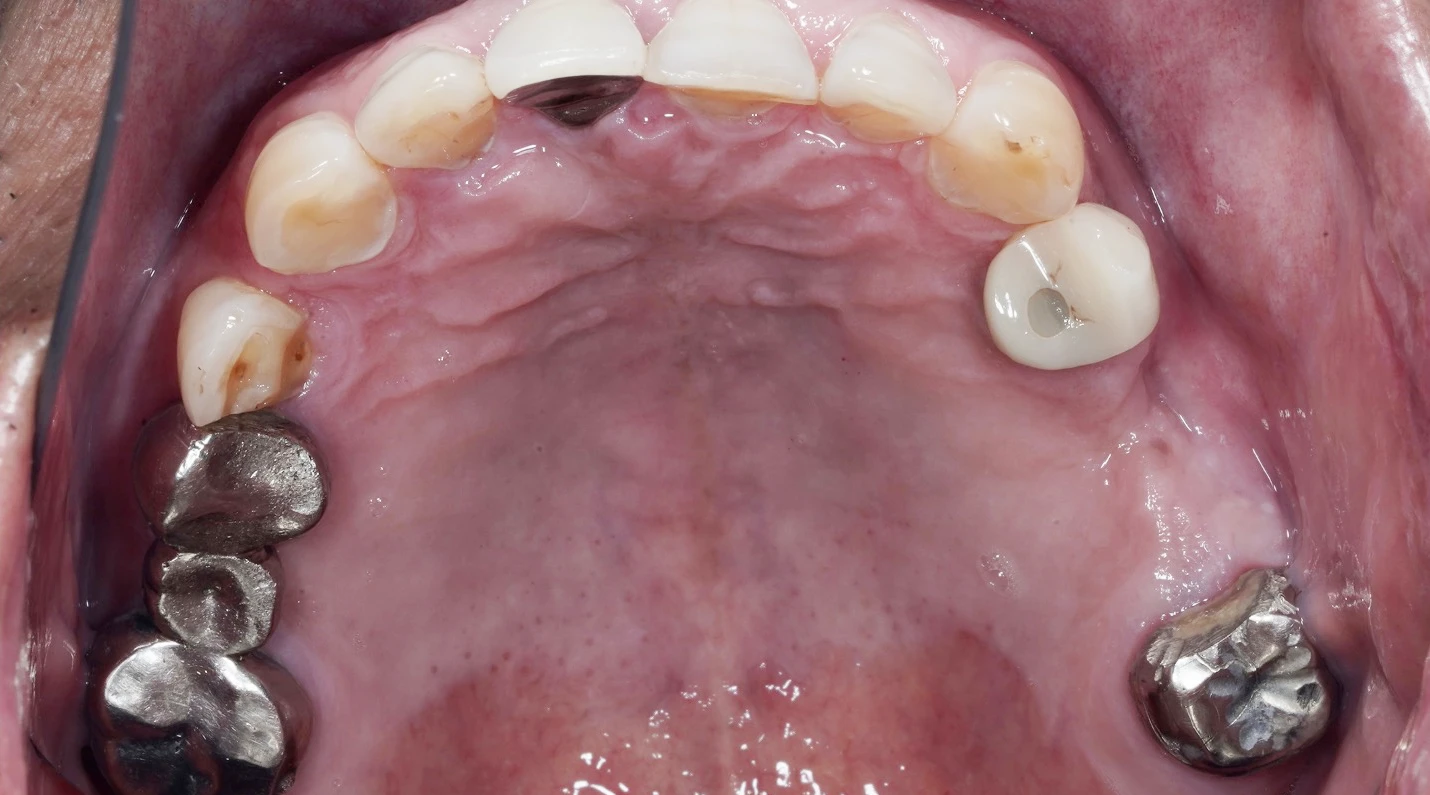

BEFORE

当院に来院された時には歯根破折(歯が割れている)している状態でした。

CT等での診断の結果抜歯と診断しました。患者様は過去にインプラント治療を複数本治療しており抜歯後はインプラント治療にて治療を行うことになりました。